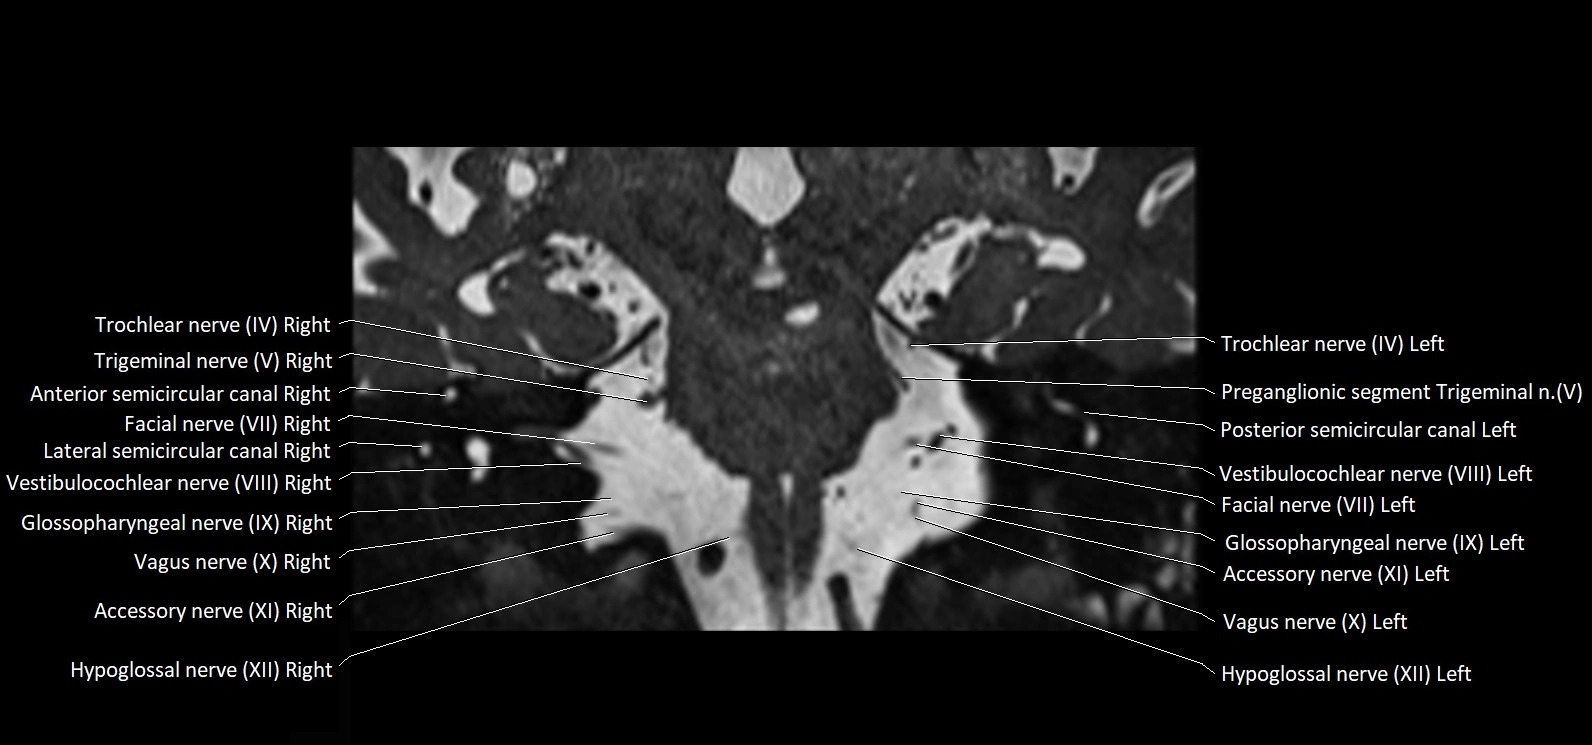

MRI Appearance

• The abducens nerve is a small, thin, linear structure

• Best visualized on high-resolution T2-weighted 3D MRI sequences (e.g., FIESTA or CISS)

• Seen as a hypointense (dark) line running from the brainstem at the pontomedullary junction, traversing the prepontine cistern, and entering Dorello’s canal under the petrosphenoidal ligament, then into the cavernous sinus, and finally the orbit

• May be challenging to visualize in standard MRI due to its small size

• Pathology may be inferred by absence, displacement, or enhancement of the nerve